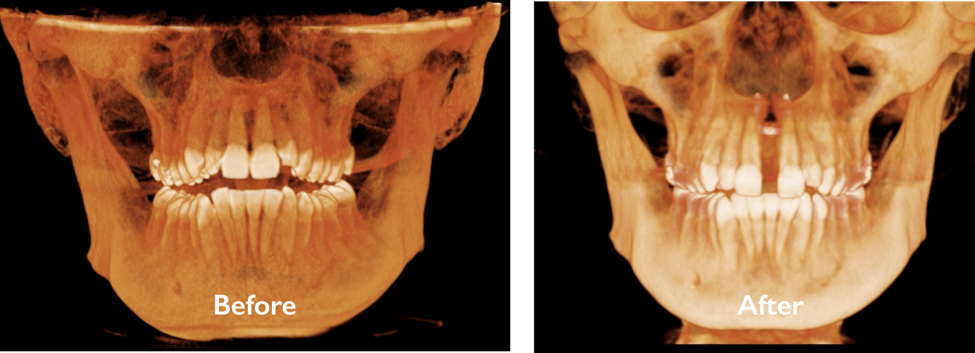

CUSTOM MARPE FOR MATURE PATIENTS

For teens and adults with underdeveloped upper jaws or airway concerns, Dr. Bockow offers custom MARPE (Miniscrew-Assisted Rapid Palatal Expansion). Unlike traditional expanders, MARPE uses precise digital planning and bone-anchored expansion to achieve results even after growth is complete.

- Widen the upper jaw and improve nasal airflow

- Reduce crowding and crossbites

- Enhance facial symmetry and bite function

- Support airway and breathing improvements

Each MARPE is customized to the patient’s anatomy for maximum comfort and effectiveness. Because of this expertise, patients frequently travel from across the country for Dr. Bockow’s specialized treatment.